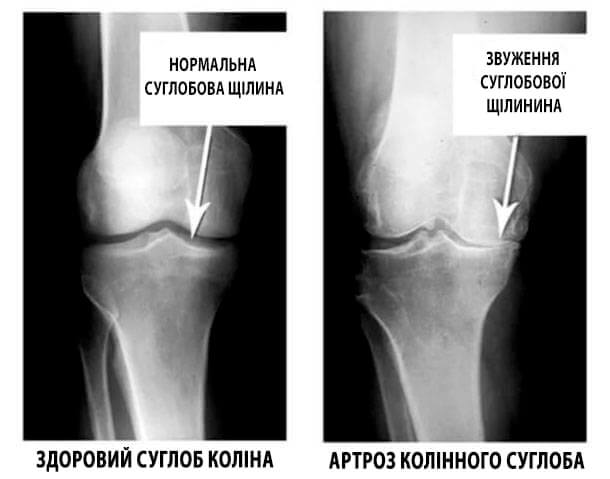

Погляньте на ці знімки, ви бачите, що на правому знімку суглобова щілина відсутня, кістки труться один об одного, викликаючи сильний біль. І цей процес дуже важко зупинити! Через пару років людина стане інвалідом і не зможе себе обслуговувати.

А. Канзюба: Насамперед, це травми та серйозні навантаження. Зайву вагу також надає сильний тиск на суглоби. Малорухливий спосіб життя, стреси, велика кількість солі і цукру в їжі все це розм'якшує хрящову тканину, зношує та стоншує її. Від кожного нового руху хрящ стирається і деформується, кістки починають тертися один об одного, викликаючи нестерпну біль.